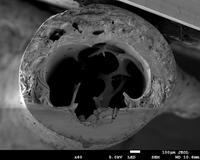

Caption: This piece shows the cross-section of a femur from a mouse after fracture toughness testing. In fracture toughness testing, the bone is notched and broken, then imaged using a scanning electron microscope. In this image, the notch is the smooth surface at the bottom of the bone. Stable growth of the crack during testing is represented by the striations in the bone surface, extending from the notch. Measuring the angle from the center of the bone cross-section to the notch edge and to the end of stable crack growth are each measured. These values can then be used to calculate properties of fracture toughness. Fracture toughness measures can help researchers understand how different treatments, diseases, etc., may impact the fracture resistance of a bone.